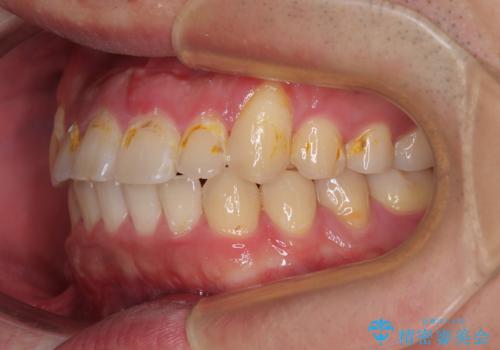

舌突出癖が改善されず、なかなか正中の隙間や上下の前歯が接触しなかったために治療が長期化してしまいました。

また、治療期間中のプラークコントロールが悪く、ブラッシング指導も奏功しなかったため、装置の周りが脱灰した状態(初期むし歯)となってしまいました。